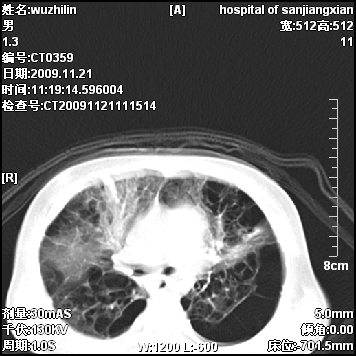

弥漫性薄壁囊腔,胸膜下及肺底部占优势,双上肺磨玻璃密度影,首先考虑特发性肺间质纤维化,其次囊性肺纤维化,肺淋巴管平滑肌瘤病嗜酸性肉芽肿等;要结合临床综合考虑。

两肺布满多个薄壁含气囊腔,以下肺居多,伴磨玻璃样密度影,左侧气胸。两肺发育不全、两肺多发肺囊肿并感染,其次考虑肺囊腺瘤。